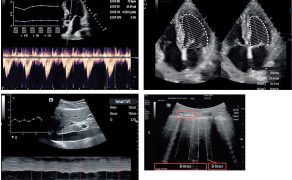

Kolejnym krokiem jest automatyczna identyfikacja struktur anatomicznych oraz wykonywanie złożonych pomiarów, które dotychczas wymagały wysokiej biegłości technicznej. W praktyce klinicznej obejmuje to m.in. automatyczną ocenę funkcji skurczowej serca, analizę przepływów, ocenę zmienności wymiarów naczyń czy identyfikację charakterystycznych artefaktów płucnych. Z punktu widzenia anestezjologii i intensywnej terapii kluczowe znaczenie ma fakt, że pomiary te wykonywane są szybko, powtarzalnie i w sposób ustandaryzowany, co znacząco ogranicza zmienność między operatorami i poprawia bezpieczeństwo podejmowanych decyzji (4).

Jednym z najbardziej przełomowych elementów tej transformacji jest rozwój systemów automatycznego labelingu, czyli kolorowego kodowania struktur anatomicznych w czasie rzeczywistym. Rozwiązania te, oparte na algorytmach uczenia maszynowego i głębokich sieciach neuronowych (m.in. architekturze U-Net), umożliwiają automatyczne rozpoznawanie i oznaczanie kluczowych struktur, takich jak nerwy, naczynia, mięśnie, powięzi czy opłucna, przy użyciu czytelnego kodu kolorystycznego. W efekcie obraz ultrasonograficzny przestaje być jedynie płaską reprezentacją anatomii, a zaczyna pełnić funkcję interaktywnego interfejsu informacyjnego (6).

Najistotniejsza zmiana zachodzi jednak na poziomie interpretacji danych. Tradycyjnie ultrasonografia była narzędziem opisowym, a lekarz samodzielnie formułował hipotezy diagnostyczne na podstawie obserwowanego obrazu. Współczesne systemy AI przesuwają ten proces w kierunku interpretacji wspomaganej algorytmicznie, w której obraz ultrasonograficzny integrowany jest z innymi danymi klinicznymi i prezentowany w postaci sugestii diagnostycznych, trendów lub wskaźników istotnych klinicznie. Sztuczna inteligencja porządkuje dane i zmniejsza obciążenie poznawcze lekarza, nie przejmując jednak odpowiedzialności za decyzję (2, 3, 7).